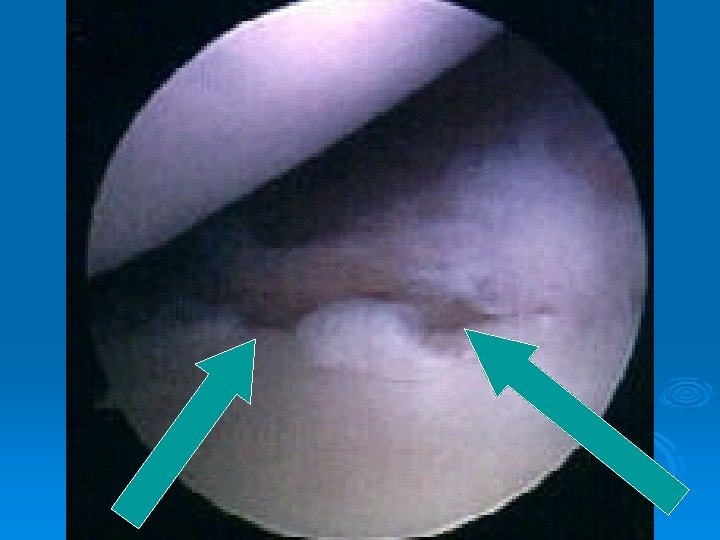

Dislocations Ø Most commonly traumatic and anterior Ø Postion of vulnerability (Abduction/ER) Ø 70% recurrence rate in patients under 22 Ø Independent of length of immobilization and physical therapy Ø Usually have a Bankart lesion (detached labrum) Ø Correlation between number of dislocations and soft tissue injury

Bony Bankart